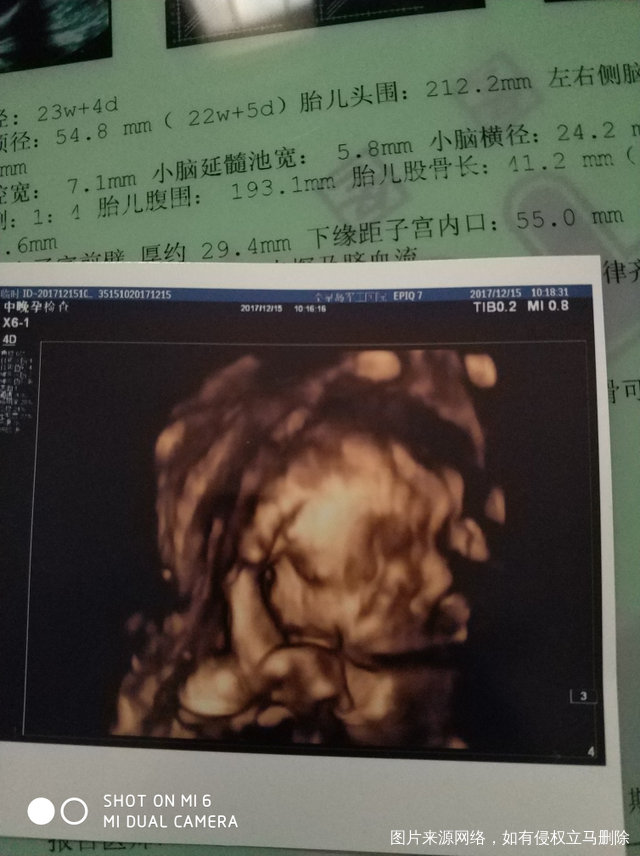

请问宝宝的手在哪啊看不懂